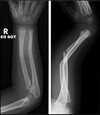

What pathology is present?

Monteggia # | One bone fractured, other bone dislocated

# What pathology is this describing? Fracture of the distal third of the radius, with posterior dislocation of the distal ulna

Galeazzi #